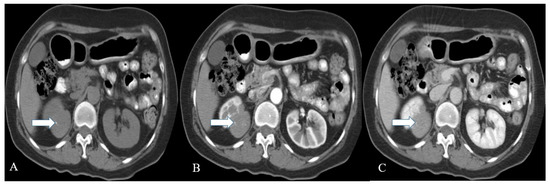

Figure 3. A 36-year-old female with renal NENs. CT of the abdomen before (A) and after oral and IV contrast administration in (B) arterial, (C) porto-venous, and (D) delayed phases reveal a 5.3 × 3.9 cm partially calcified mass (arrows) arising from the left kidney, extending to the left perinephric space, and abutting the tail of the pancreas. Pathology revealed small-cell carcinoma with neuroendocrine differentiation.